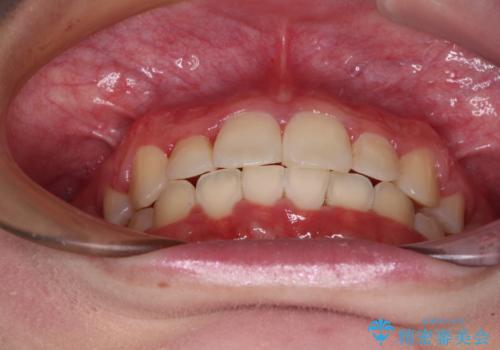

インビザラインが続けられない ワイヤー矯正での抜歯矯正 その2

- 八重歯やデコボコをインビザラインで治療したいとのことで来院された患者様です。

インビザライン単体で治療を行うには叢生が強いと判断されたため、事前にワイヤー装置で抜歯矯正を行い、ある程度改善してからインビザラインにて仕上げていくこととしました。